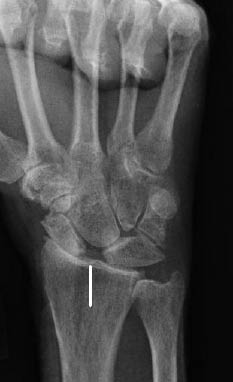

Figure 9: Perilunate Dislocation with Dorsal Displacement of the Capitate

The diagnostic imaging includes standard PA and lateral radiographs. When reviewing these plain radiographs, one should pay close attention to the space between the individual carpal bones on the PA view. The space between the bones should be uniform. The presence of a gap greater than 2 mm is indicative of ligamentous injury and possible carpal instability.32 Gilula described radiographic lines for discovering carpal bone injuries due to ligamentous and bony injuries of the wrist.33 In an uninjured wrist, the articular surfaces of the proximal and distal carpal rows form smooth arcs at the radiocarpal and midcarpal articulations.32 (See Figure 6.) A disruption of any of these lines is indicative of carpal instability or possible injury.32 The lateral view of the wrist is often the best view to appreciate a perilunate dislocation. Remember the "3 Cs" sign when examining a lateral radiograph of the wrist. The "3 Cs" are formed by the articulations of the distal radius, lunate, capitate, and base of the third metacarpal, respectively. (See Figures 7 and 8.) The arrangement of the 3 Cs in a perilunate dislocation is disrupted at the level of the capitate, which represents the third C. It is displaced dorsally toward the lunate, which remains in contact with the radius.12 (See Figure 9.)